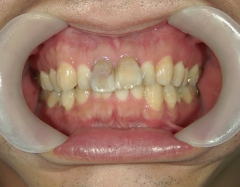

矯正歯科 治療後矯正歯科 全顎ワイヤー矯正 治療後矯正歯科(全顎ワイヤー矯正)治療後

矯正歯科 治療後 E-AMXというセラミックにて左右上1番を被せ直しました。